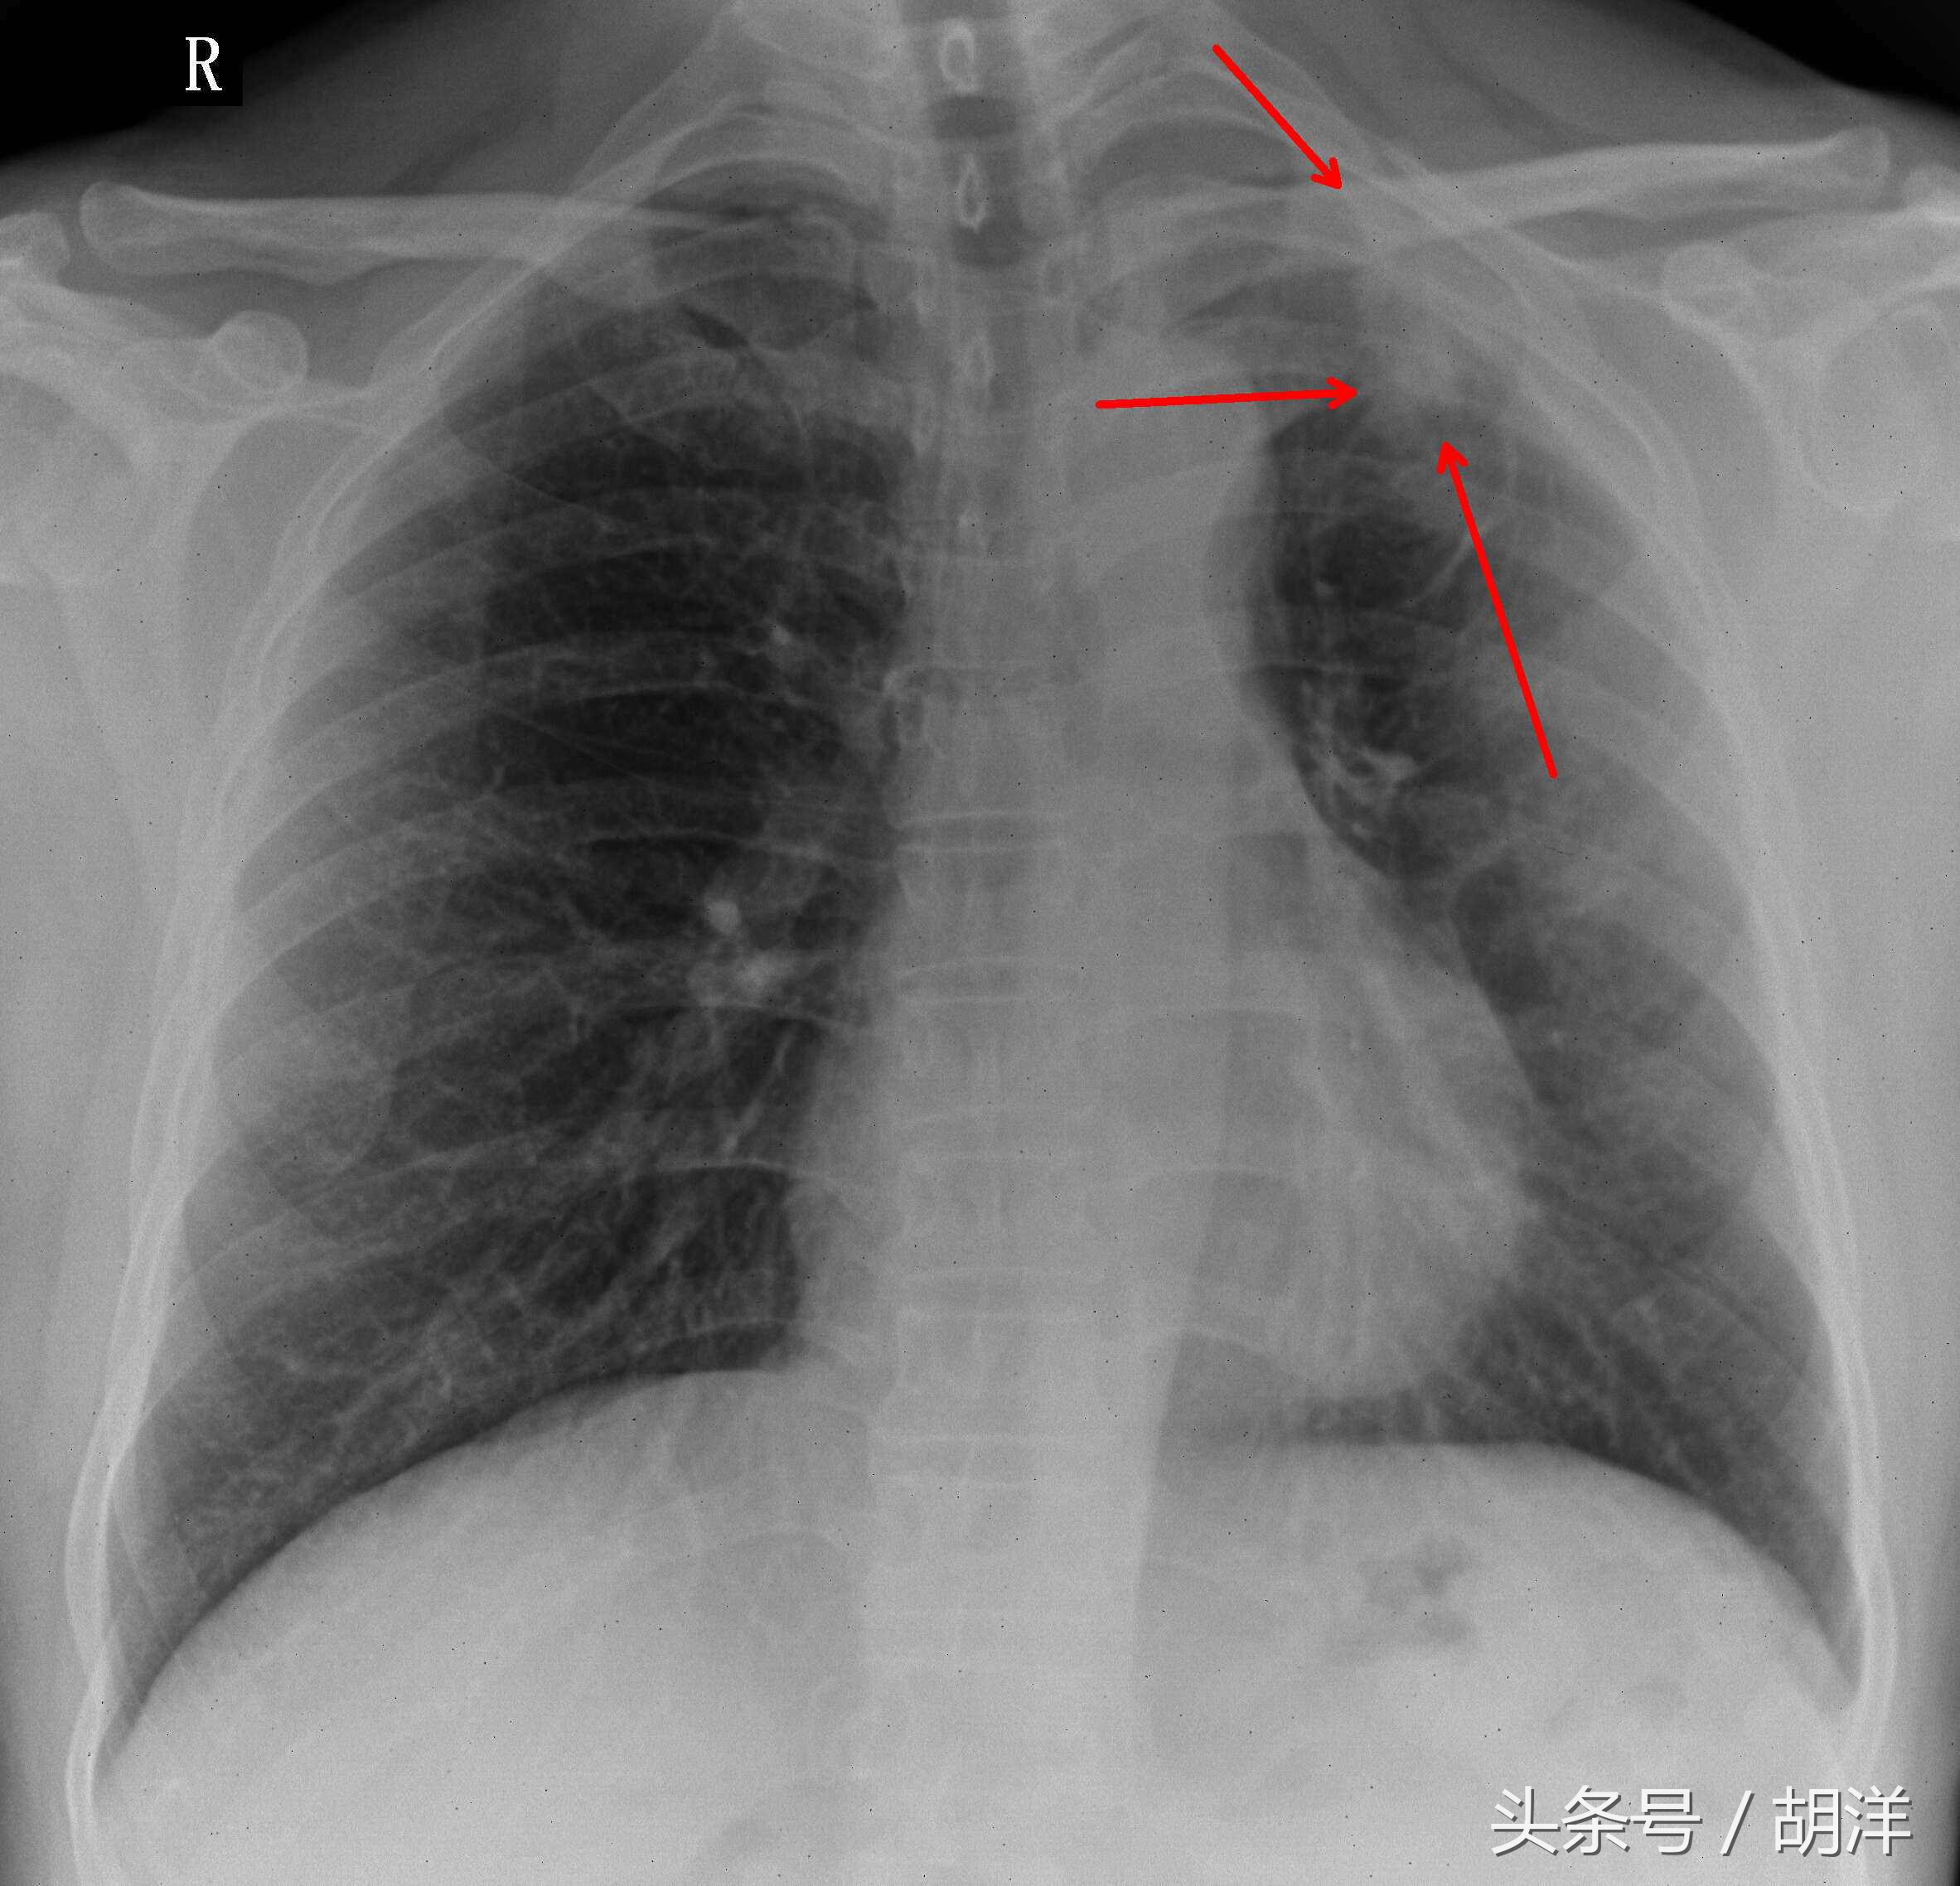

虽然钙化灶是结核愈合的标志,但只能代表钙化灶所在的部位愈合,并不能代表钙化灶以外的其他部位不是活动性结核,事实上肺结核的特点就是以多发的多形态的病灶为表现,钙化只能说明钙化的部位愈合,其他非钙化部位是否有活动性结核并不能确定。

钙化灶并不是结核所特有

钙化灶并不是陈旧性结核所特有的,多种感染性疾病都有可能在慢性发展过程中出现钙化现象,已经完全愈合的钙化病灶基本上不能完全消掉,大部分也不会对身体造成严重的损害。